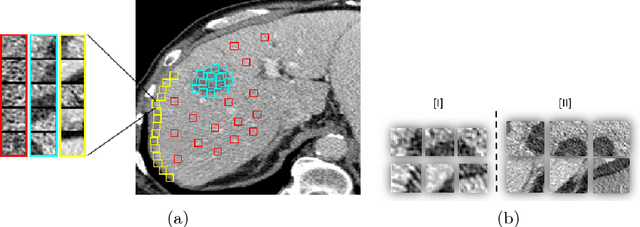

Abstract:Deep learning methods, and in particular convolutional neural networks (CNNs), have led to an enormous breakthrough in a wide range of computer vision tasks, primarily by using large-scale annotated datasets. However, obtaining such datasets in the medical domain remains a challenge. In this paper, we present methods for generating synthetic medical images using recently presented deep learning Generative Adversarial Networks (GANs). Furthermore, we show that generated medical images can be used for synthetic data augmentation, and improve the performance of CNN for medical image classification. Our novel method is demonstrated on a limited dataset of computed tomography (CT) images of 182 liver lesions (53 cysts, 64 metastases and 65 hemangiomas). We first exploit GAN architectures for synthesizing high quality liver lesion ROIs. Then we present a novel scheme for liver lesion classification using CNN. Finally, we train the CNN using classic data augmentation and our synthetic data augmentation and compare performance. In addition, we explore the quality of our synthesized examples using visualization and expert assessment. The classification performance using only classic data augmentation yielded 78.6% sensitivity and 88.4% specificity. By adding the synthetic data augmentation the results increased to 85.7% sensitivity and 92.4% specificity. We believe that this approach to synthetic data augmentation can generalize to other medical classification applications and thus support radiologists' efforts to improve diagnosis.

Abstract:In this paper, we present a data augmentation method that generates synthetic medical images using Generative Adversarial Networks (GANs). We propose a training scheme that first uses classical data augmentation to enlarge the training set and then further enlarges the data size and its diversity by applying GAN techniques for synthetic data augmentation. Our method is demonstrated on a limited dataset of computed tomography (CT) images of 182 liver lesions (53 cysts, 64 metastases and 65 hemangiomas). The classification performance using only classic data augmentation yielded 78.6% sensitivity and 88.4% specificity. By adding the synthetic data augmentation the results significantly increased to 85.7% sensitivity and 92.4% specificity.

Abstract:Automatic detection of liver lesions in CT images poses a great challenge for researchers. In this work we present a deep learning approach that models explicitly the variability within the non-lesion class, based on prior knowledge of the data, to support an automated lesion detection system. A multi-class convolutional neural network (CNN) is proposed to categorize input image patches into sub-categories of boundary and interior patches, the decisions of which are fused to reach a binary lesion vs non-lesion decision. For validation of our system, we use CT images of 132 livers and 498 lesions. Our approach shows highly improved detection results that outperform the state-of-the-art fully convolutional network. Automated computerized tools, as shown in this work, have the potential in the future to support the radiologists towards improved detection.